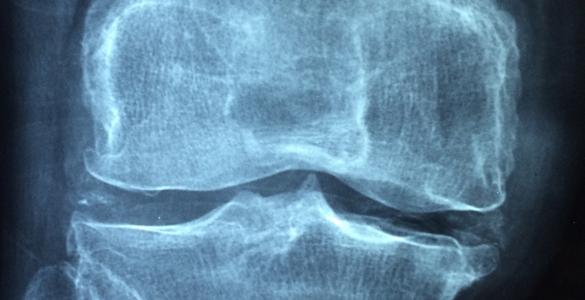

There are many different types of arthritis and chronic MSK conditions, including osteoarthritis, inflammatory arthritis, connective tissue diseases, back pain, bone disease (such as osteoporosis), soft tissue rheumatism, and chronic musculoskeletal pain. Osteoarthritis is the most common form of arthritis. Often thought of as ‘wear and tear’ of the joints, it affects people as they get older but is also common amongst people of working age. Treatment includes pain medication, lifestyle measures (e.g. weight management and exercise), and in severe cases joint replacement surgery. The Chartered Society of Physiotherapy reports that almost half a million people are living with osteoarthritis in Wales.